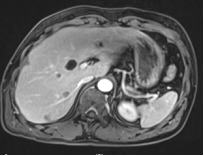

(2022.06.05) MR:1.右肝多发结节,考虑转移瘤可能2.左肾占位,错构瘤可能,MT待排3.双肾多发囊肿。(右肝多发结节,大约6个,主要集中在右肝,最大直径约2.8cm)。

image.pngimage.png